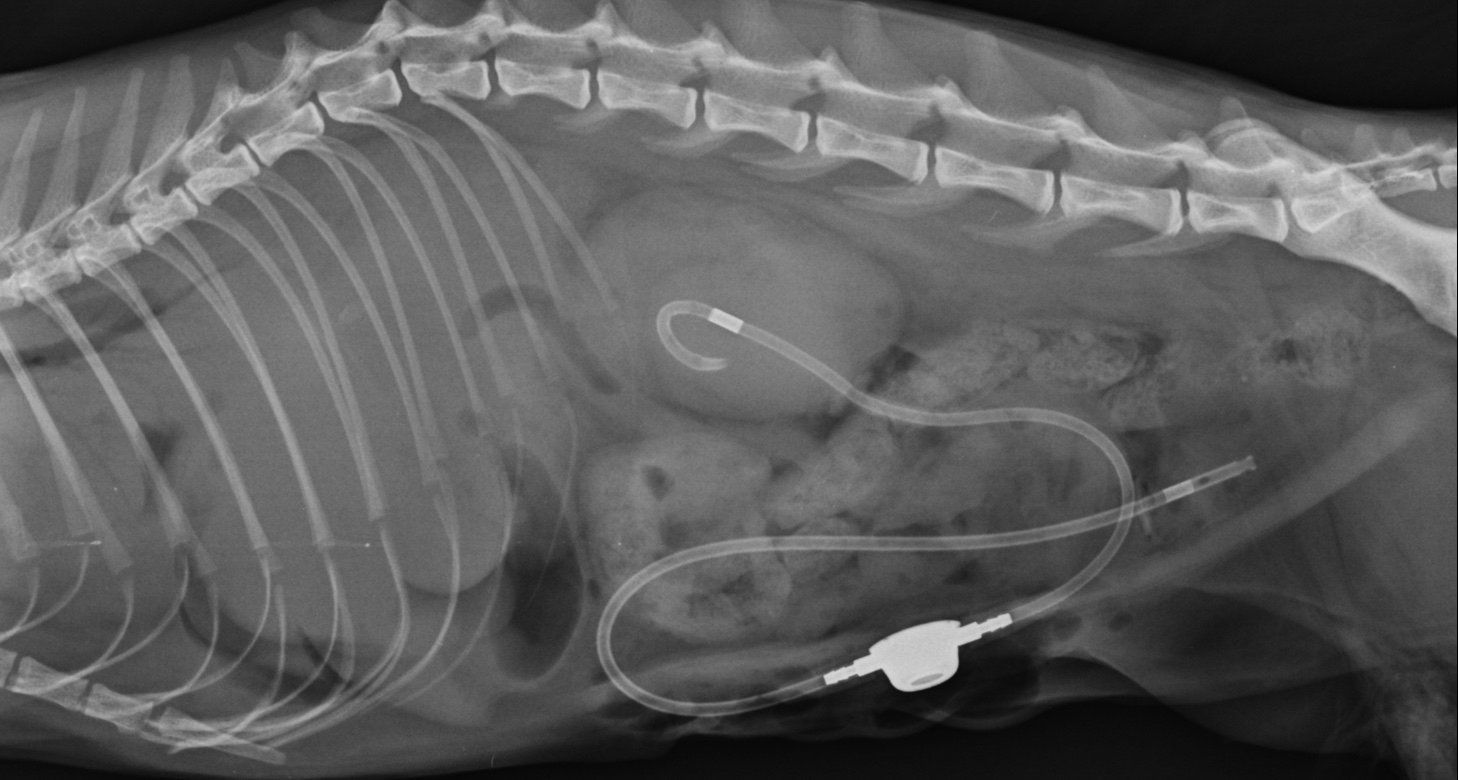

Para que el paciente tolere mejor la cirugía y la anestesia, es recomendable operar a partir de los 2 meses de edad. Si fuera necesario se podría colocar una sonda nasogástrica para garantizar su alimentación y poder posponer la cirugía el tiempo necesario para que sea adecuado someterle a cirugía.

La técnica más frecuente para esta patología es realizar un flap de 180º del paladar duro. Se puede utilizar tanto sutura monofilamento como multifilamento para evitar que los puntos molesten en la cavidad oral al paciente. Se realizan puntos en U para liberar tensión. Como en toda cirugía reconstructiva es muy importante respetar la vascularización del tejido, y dejar la mínima tensión en los tejidos.

A continuación les mostramos imágenes de la cirugía: